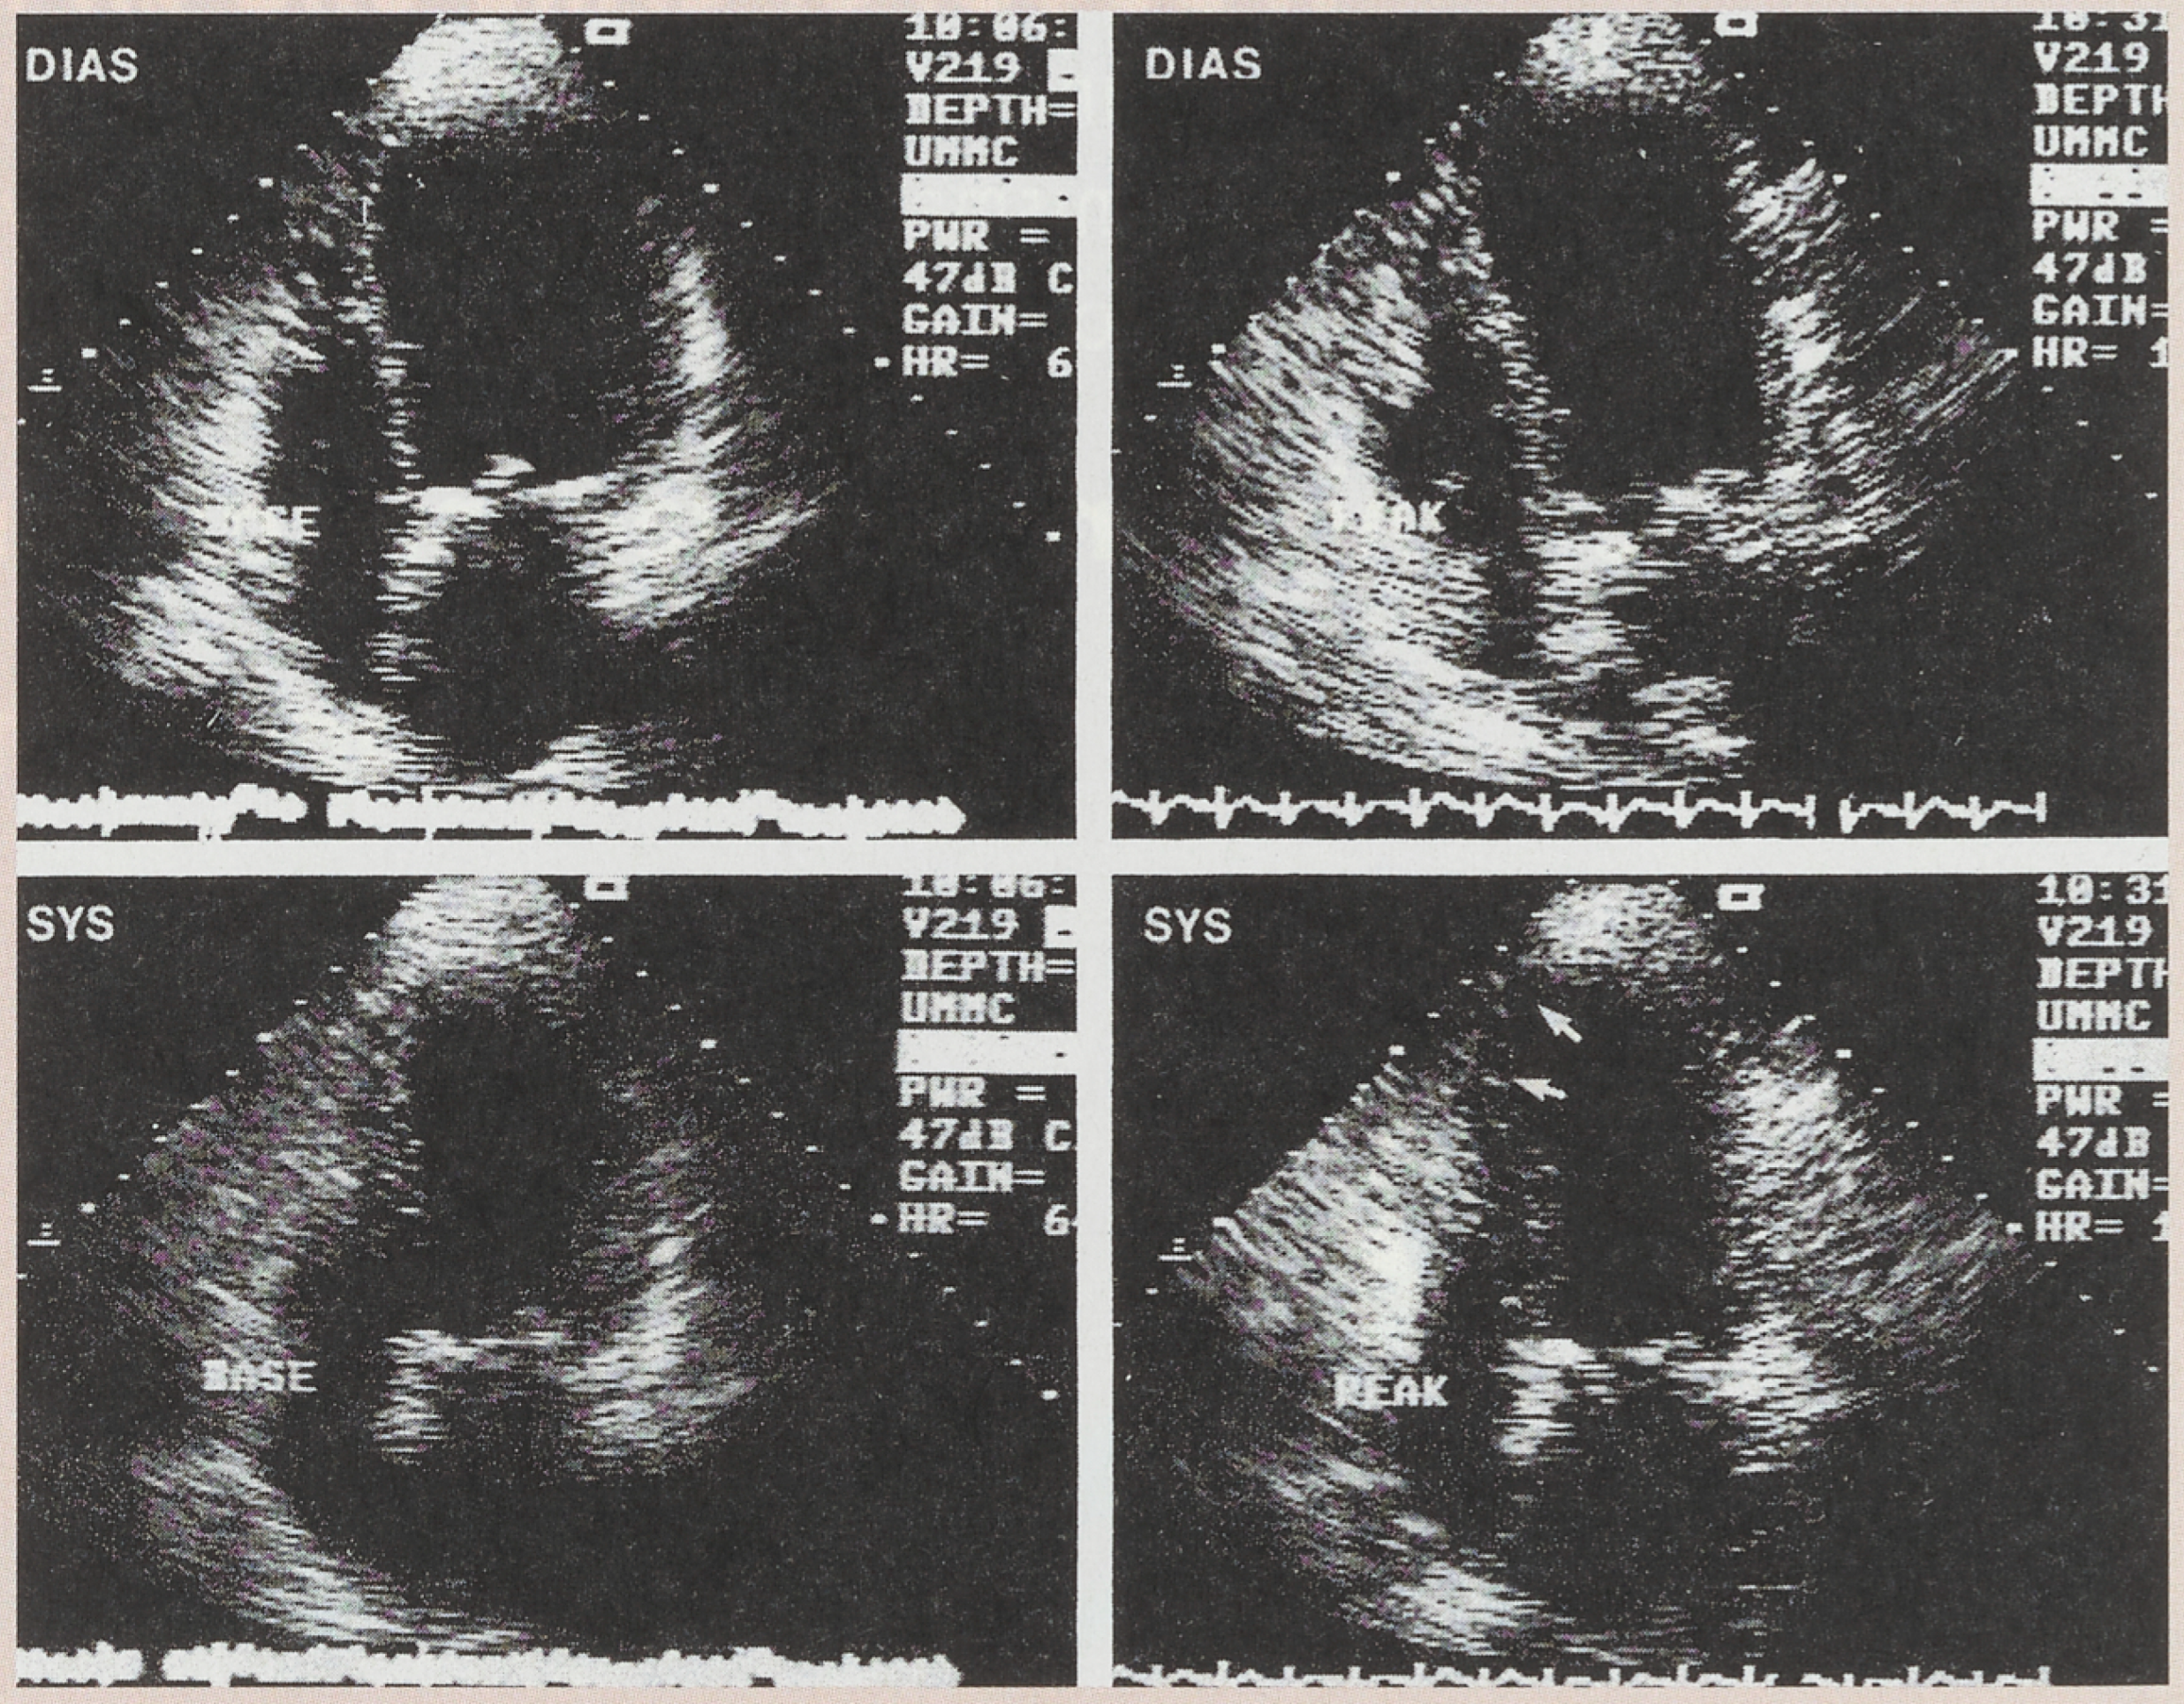

Echocardiographie Sous Stress

- Marcovitz, P.; Armstrong, W. Accuracy of dobutamine stress echocardiography in detection of coronary artery disease. Am. J. Cardiol. 1997, 69, 1269–1275. [Google Scholar] [CrossRef]